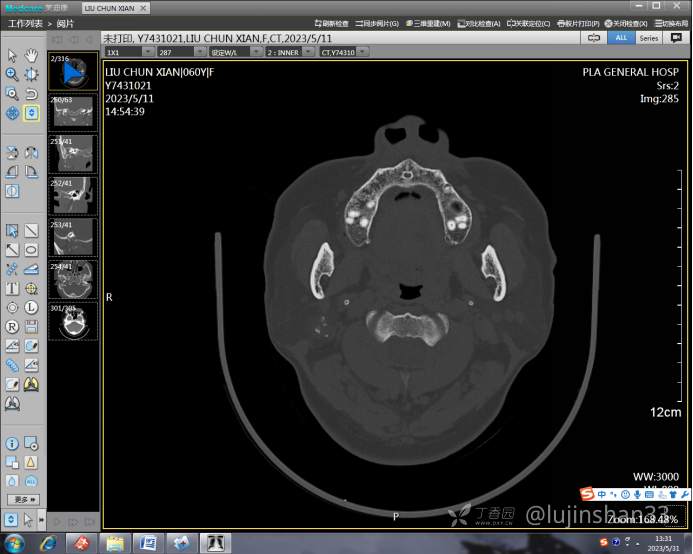

(2023-05-12 10:15,本院)行CT(颅脑)检查提示:右侧颞骨广泛骨质破坏,伴巨大软组织肿块,性质待定,考虑肿瘤性病变,颈静脉球瘤?软骨源性肿瘤?请结合临床及病理进一步明确。